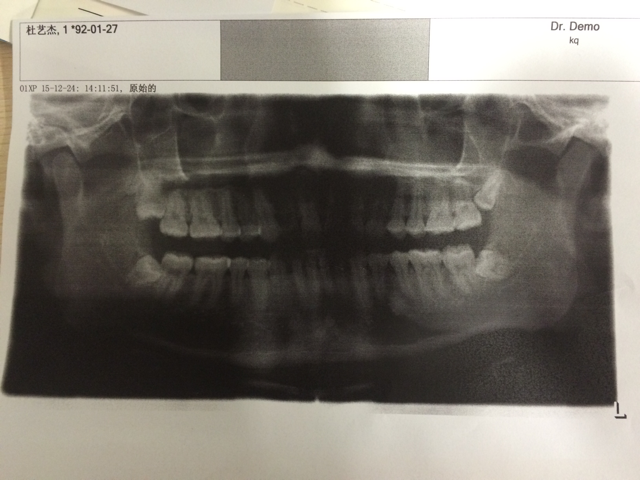

ÎÒÏÖÔÚ23Ë꣬ÕÕÇú¶ÏµÄʱºò£¬ÓÐÖdzݣ¬³¤µÃÍáÁË£¬µ«ÊÇÖdzݻ¹Ã»ÓÐðͷ£¬ÎÒÏÖÔÚ»¹ÊÇ28¿ÅÑÀ£¬ÕâÖÖÇé¿ö°Î²»°ÎÑÀÄØ£¿ @carci ·¢×ÔСľ³æIOS¿Í»§¶Ë |

Âñ·ü×èÉú£¬½¨Ò龡Ôç°Î³ý¡£ÂñÔÚ¹ÇÍ·Àïδ±ØÊǺÃÊ¡£ ·¢×ÔСľ³æIOS¿Í»§¶Ë |

ÎÒ°ÎÁËÒ»±ß£¬ÁíÍâÒ»±ß²»Ïë°ÎÁË£¬µ«ÊÇÒ»³ÔÌðµÄ£¬ËáµÄ£¬ÀäµÄ¶«Î÷Á¢¿ÌºÜÍ´ ·¢×ÔСľ³æAndroid¿Í»§¶Ë |